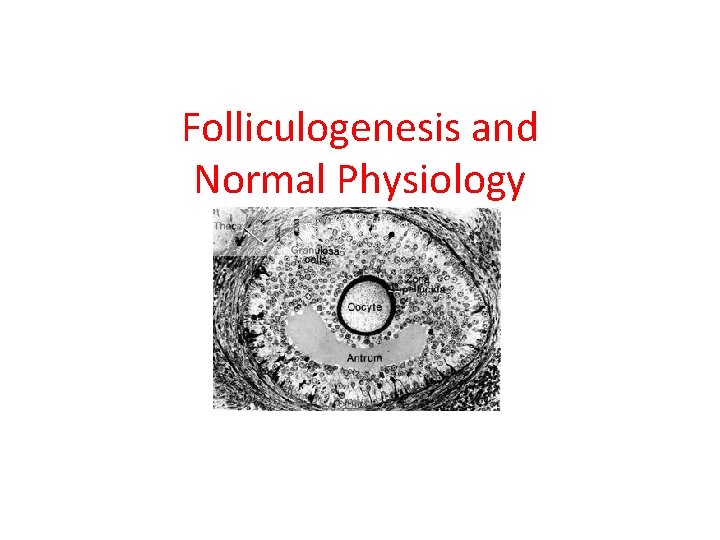

Folliculogenesis and Normal Physiology